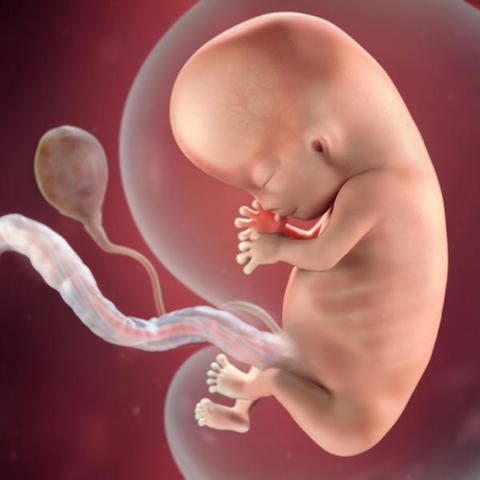

• Semana 9

Semana 9

Se forman los pezones y los folículos pilosos.

Los brazos crecen y se desarrollan los codos.

Se pueden observar los dedos del pie del bebé.

Todos los órganos esenciales del bebé han comenzado a crecer.